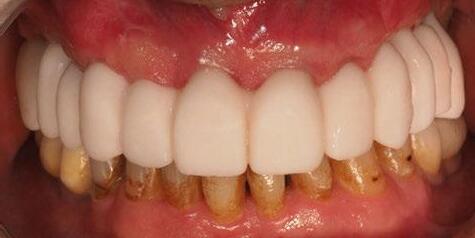

5. Fase protésica definitiva

A los 4 meses, se retiró la prótesis provisional, verificando la